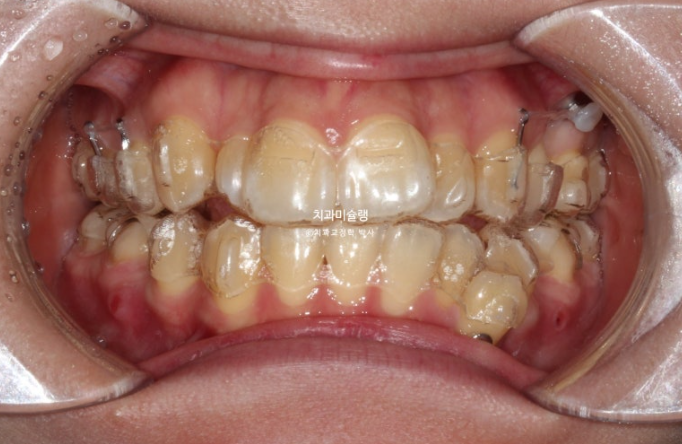

24.03

어금니 쓰러짐을 방지하고자 나사도 심고 고무줄도 걸었습니다.

그러나 치료도중 개인사로 인해 15시간밖에 못 끼던 시기가 있어서 이때 일부 어금니가 쓰러졌습니다.

어금니가 쓰러지면 장치가 일부 치아에서 뜨게 되는 현상이 나타납니다.

끼는 시간이 부족해서 10일마다 교체하던 시기도 있었지만 1년 2개월 후 드디어 56개 장치를 모두 낀 모습입니다.